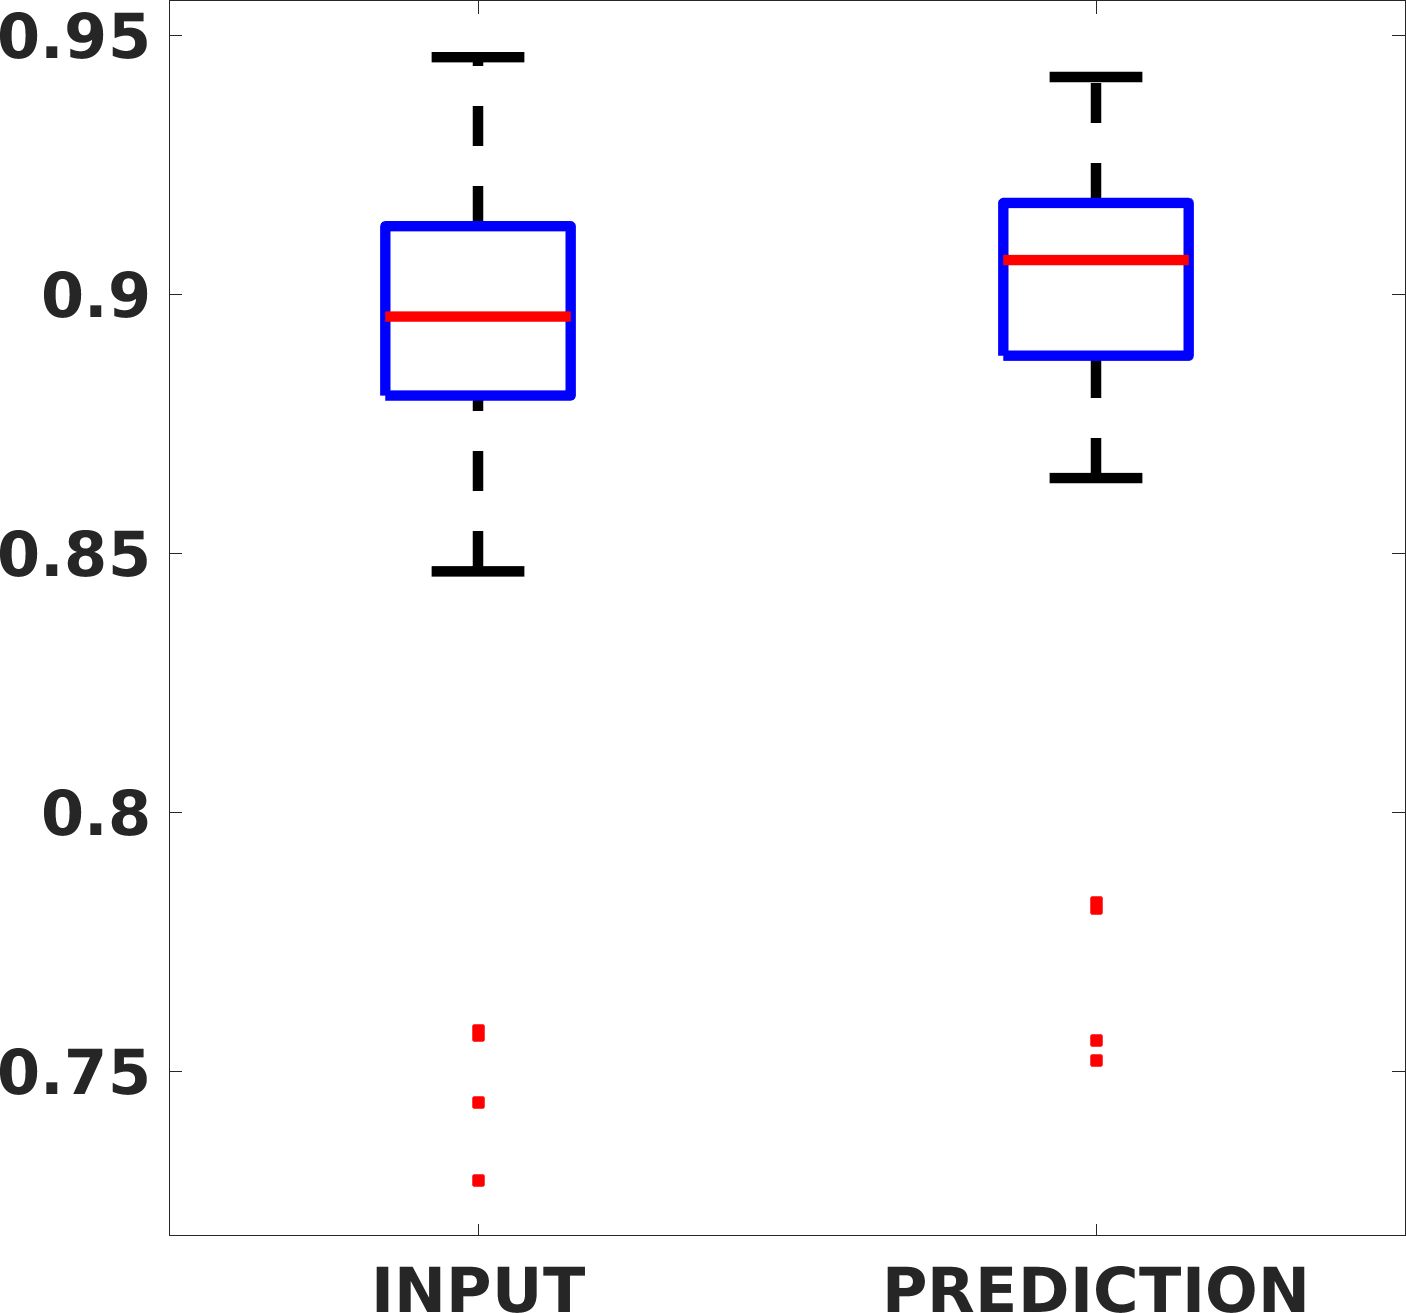

Fig. 7(a-b-c, left) shows the box plot of the statistics of the PSNR on three different anatomical districts, comparing the target images with the prediction and the cubic convolution, respectively. The metrics are computed on a data set of 200 images of the same district and with the same up-sampling factor. We report that the PSNR median value improves of on obstetric 2X raw images, on cardiac 2X raw images, and on abdominal raw 4X images.

Fig. 7(a-b-c, right) shows the histogram of the absolute value of the error with respect to the target image, of the prediction and Cubic convolution results, respectively. The histograms show the number of pixels where the prediction error is lower than 5 (i.e., the first bin of the histogram), which means very similar to the target when visually analysing the images. From the Cubic convolution to the predicted images, this value increases of on obstetric 4X raw images, on cardiac 4X raw images, and on abdominal 4X raw images.

Fig. 8 shows the box plot of the SSIM (a-b-c, left) and MAE (a-b-c, right) quantitative metrics, as performed for PSNR metric. Also, these metrics show that our method improves the results of Cubic convolution both in terms of average value and variability. For example, the SSIM median value improves of on obstetric 4X images and the MAE median value improves of on cardiac 2X images.

Fig. 17 (left) shows the box plot of the quantitative metrics, comparing the target images with the prediction and the Cubic convolution, respectively. The PSNR metric is computed on a data set of 200 images, belonging to the same district, and with the same up-sampling factor. Analysing the obstetric anatomical district and concerning the corresponding raw images (Fig. 7 (a, left)), the denoising allows the network to significantly improve the results of the up-sampling and the prediction. In particular, comparing the target images with the predicted images, the median PSNR value of obstetric 2X denoised images is 51.8, compared to the median PSNR value of obstetric 2X raw images which is 36.9.

Fig. 17 (right) shows the histogram of the absolute value of the error with respect to the target, of the prediction and Cubic convolution respectively. This result shows that our framework increase of and (2X and 4X, respectively) the number of pixels where the prediction error is lower than 5, which is very similar to the target when visually analysing the images, and improved with respect to the learning framework applied to raw images. According to Fig. 18, our method improves the accuracy of Cubic convolution. For example, the SSIM increases of on cardiac 2X and the MAE increases of on abdominal 4X.